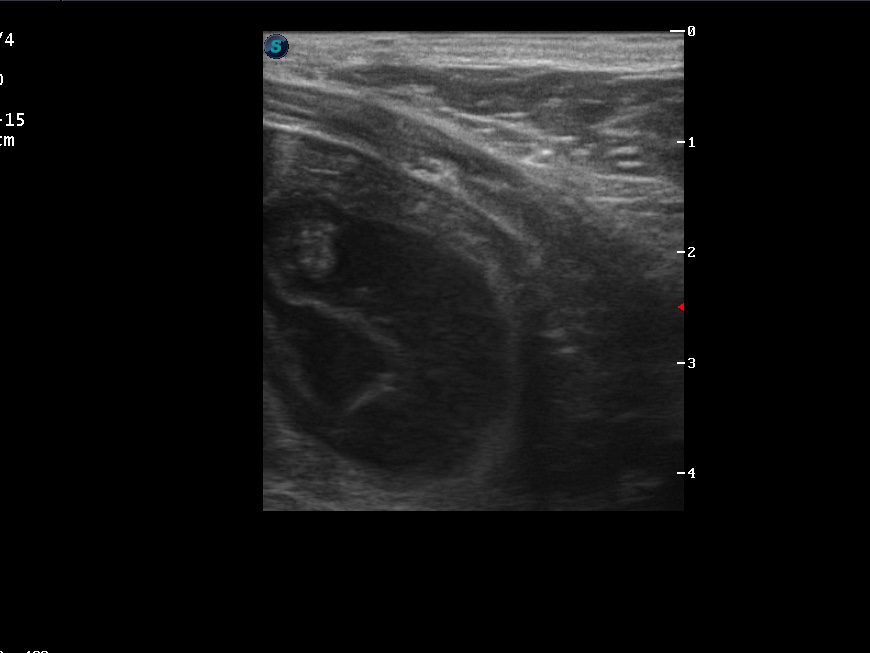

06.04.20 (43. Trächtigkeitstag)

So langsam wächst Ellas Bäuchlein. 🥰